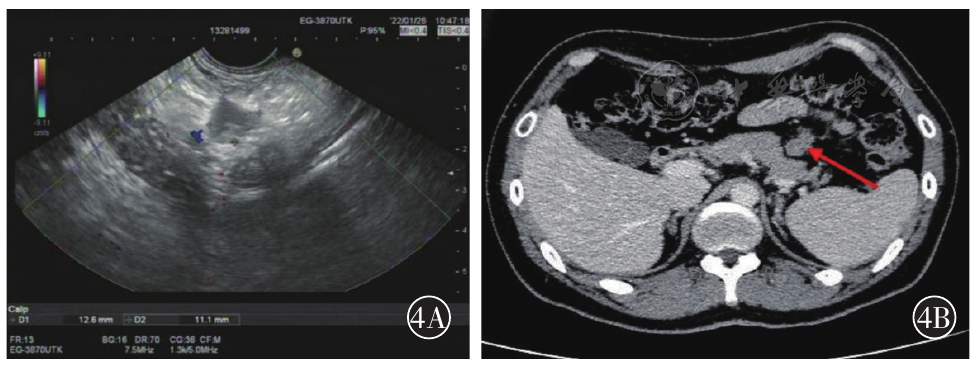

图4 A为超声内镜提示胰颈部前方不规则病变;B为CT提示胰体部前方结节状软组织密度影